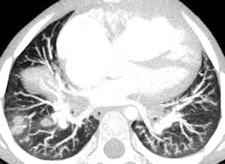

CT is vital for evaluating the central airway, mediastinal structures, and lung parenchyma, plus it's more sensitive than plain radiographs in detection of structural changes within the lungs, but CT examinations must be clinically justified by the referring clinician and radiologist.

MDCT using a low radiation dose protocol is the best diagnostic tool for assessing the central airway, cardiovascular and mediastinal abnormalities, and the lung parenchyma in children, and the relevant information can be acquired with a single-volumetric data set acquisition, she stated. Using thin-slice collimation acquisition with inherent isotropic resolution, the image data can be manipulated and reformatted to display 2D and 3D images with the same spatial resolution as the axial images, thus enhancing diagnostic accuracy and providing data that can be used in presurgical planning and patient management.